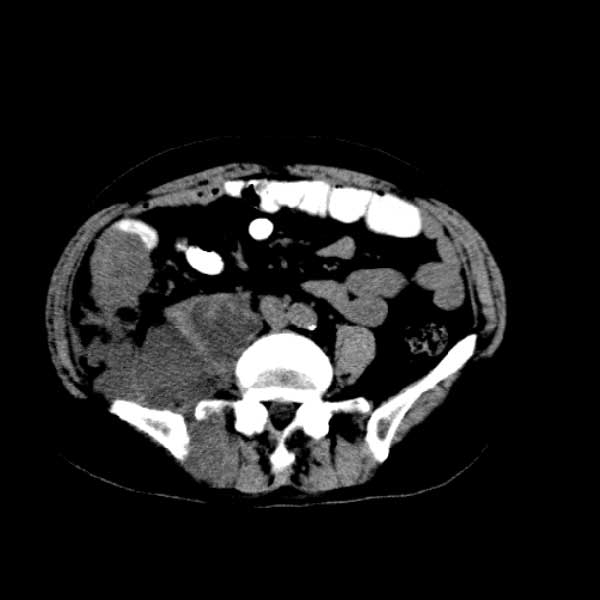

标题: CT13513:男 71 腹部疼痛20余天,近几天高热就诊,骨窗未见异 [打印本页]

标题: CT13513:男 71 腹部疼痛20余天,近几天高热就诊,骨窗未见异

考虑感染性病变可能性大,起源于阑尾?

感染,脓肿形成

考虑为化脓性阑尾炎.脓肿形成.及多肌肉累及.

考虑右侧腰大肌脓肿,向右髂窝、右腹股沟流注。

支持化脓性阑尾炎伴右髂窝脓肿、腰大肌腰方肌脓肿形成。

考虑腹腔及盆腔化脓性炎症,累及右侧髋关节及腹股沟区.

首先考虑化脓性阑尾炎伴腰大肌、腰方肌脓肿,不除外回盲部结核。

回盲部癌待排除。

患者肠镜检查考虑结肠癌,病理证实

患者肠镜检查考虑结肠癌,病理证实。肺部ct可见多发结节,考虑转移